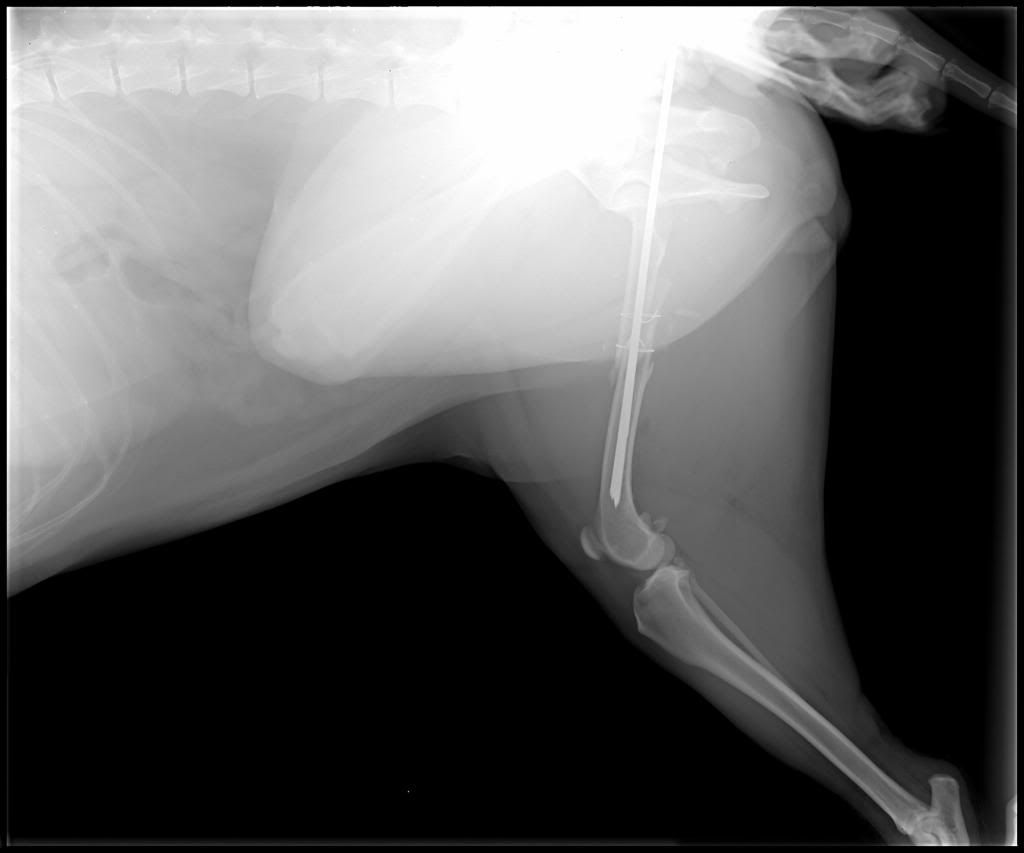

As some of you may recall from previous threads about dogs in public places, I have a service dog. Last Saturday she snuck out of the house while we were doing a kitchen renovation and got hit by a car. We were very lucky that the lady who hit her stopped and came looking for us, since my dog may have died of shock before we ever realized she was missing. Anyway, her back leg was broken into three pieces, but there was nothing else wrong with her (no internal bleeding or head trauma). Still, the emergency vet was telling us it would cost $3,000-$5,000(!) to fix her leg.

Then I found the people at James Landing Veterinary Hospital. Their first concern was that my dog was comfortable and the first thing they wanted from me were her x-rays. They promised that they would do everything they could to take care of my dog, and they have. Because she's my service dog they cut the price to a third of what every place else was quoting: a difficult price to pay but not impossible with the help of friends and family. They sent me that day to their sister clinic, the Thomasville Veterinary Hospital. She got her surgery Tuesday and is doing well. We expect to have her home late next week and the vet says she'll have a full recovery! They even think her leg will be strong enough for her to perform her mobility work of helping me get up off the ground if I fall.